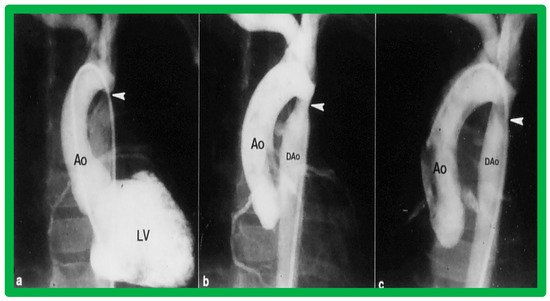

4.3. Aortic Coarctation–Native

Revisit BA in the Neonate and Young Infant